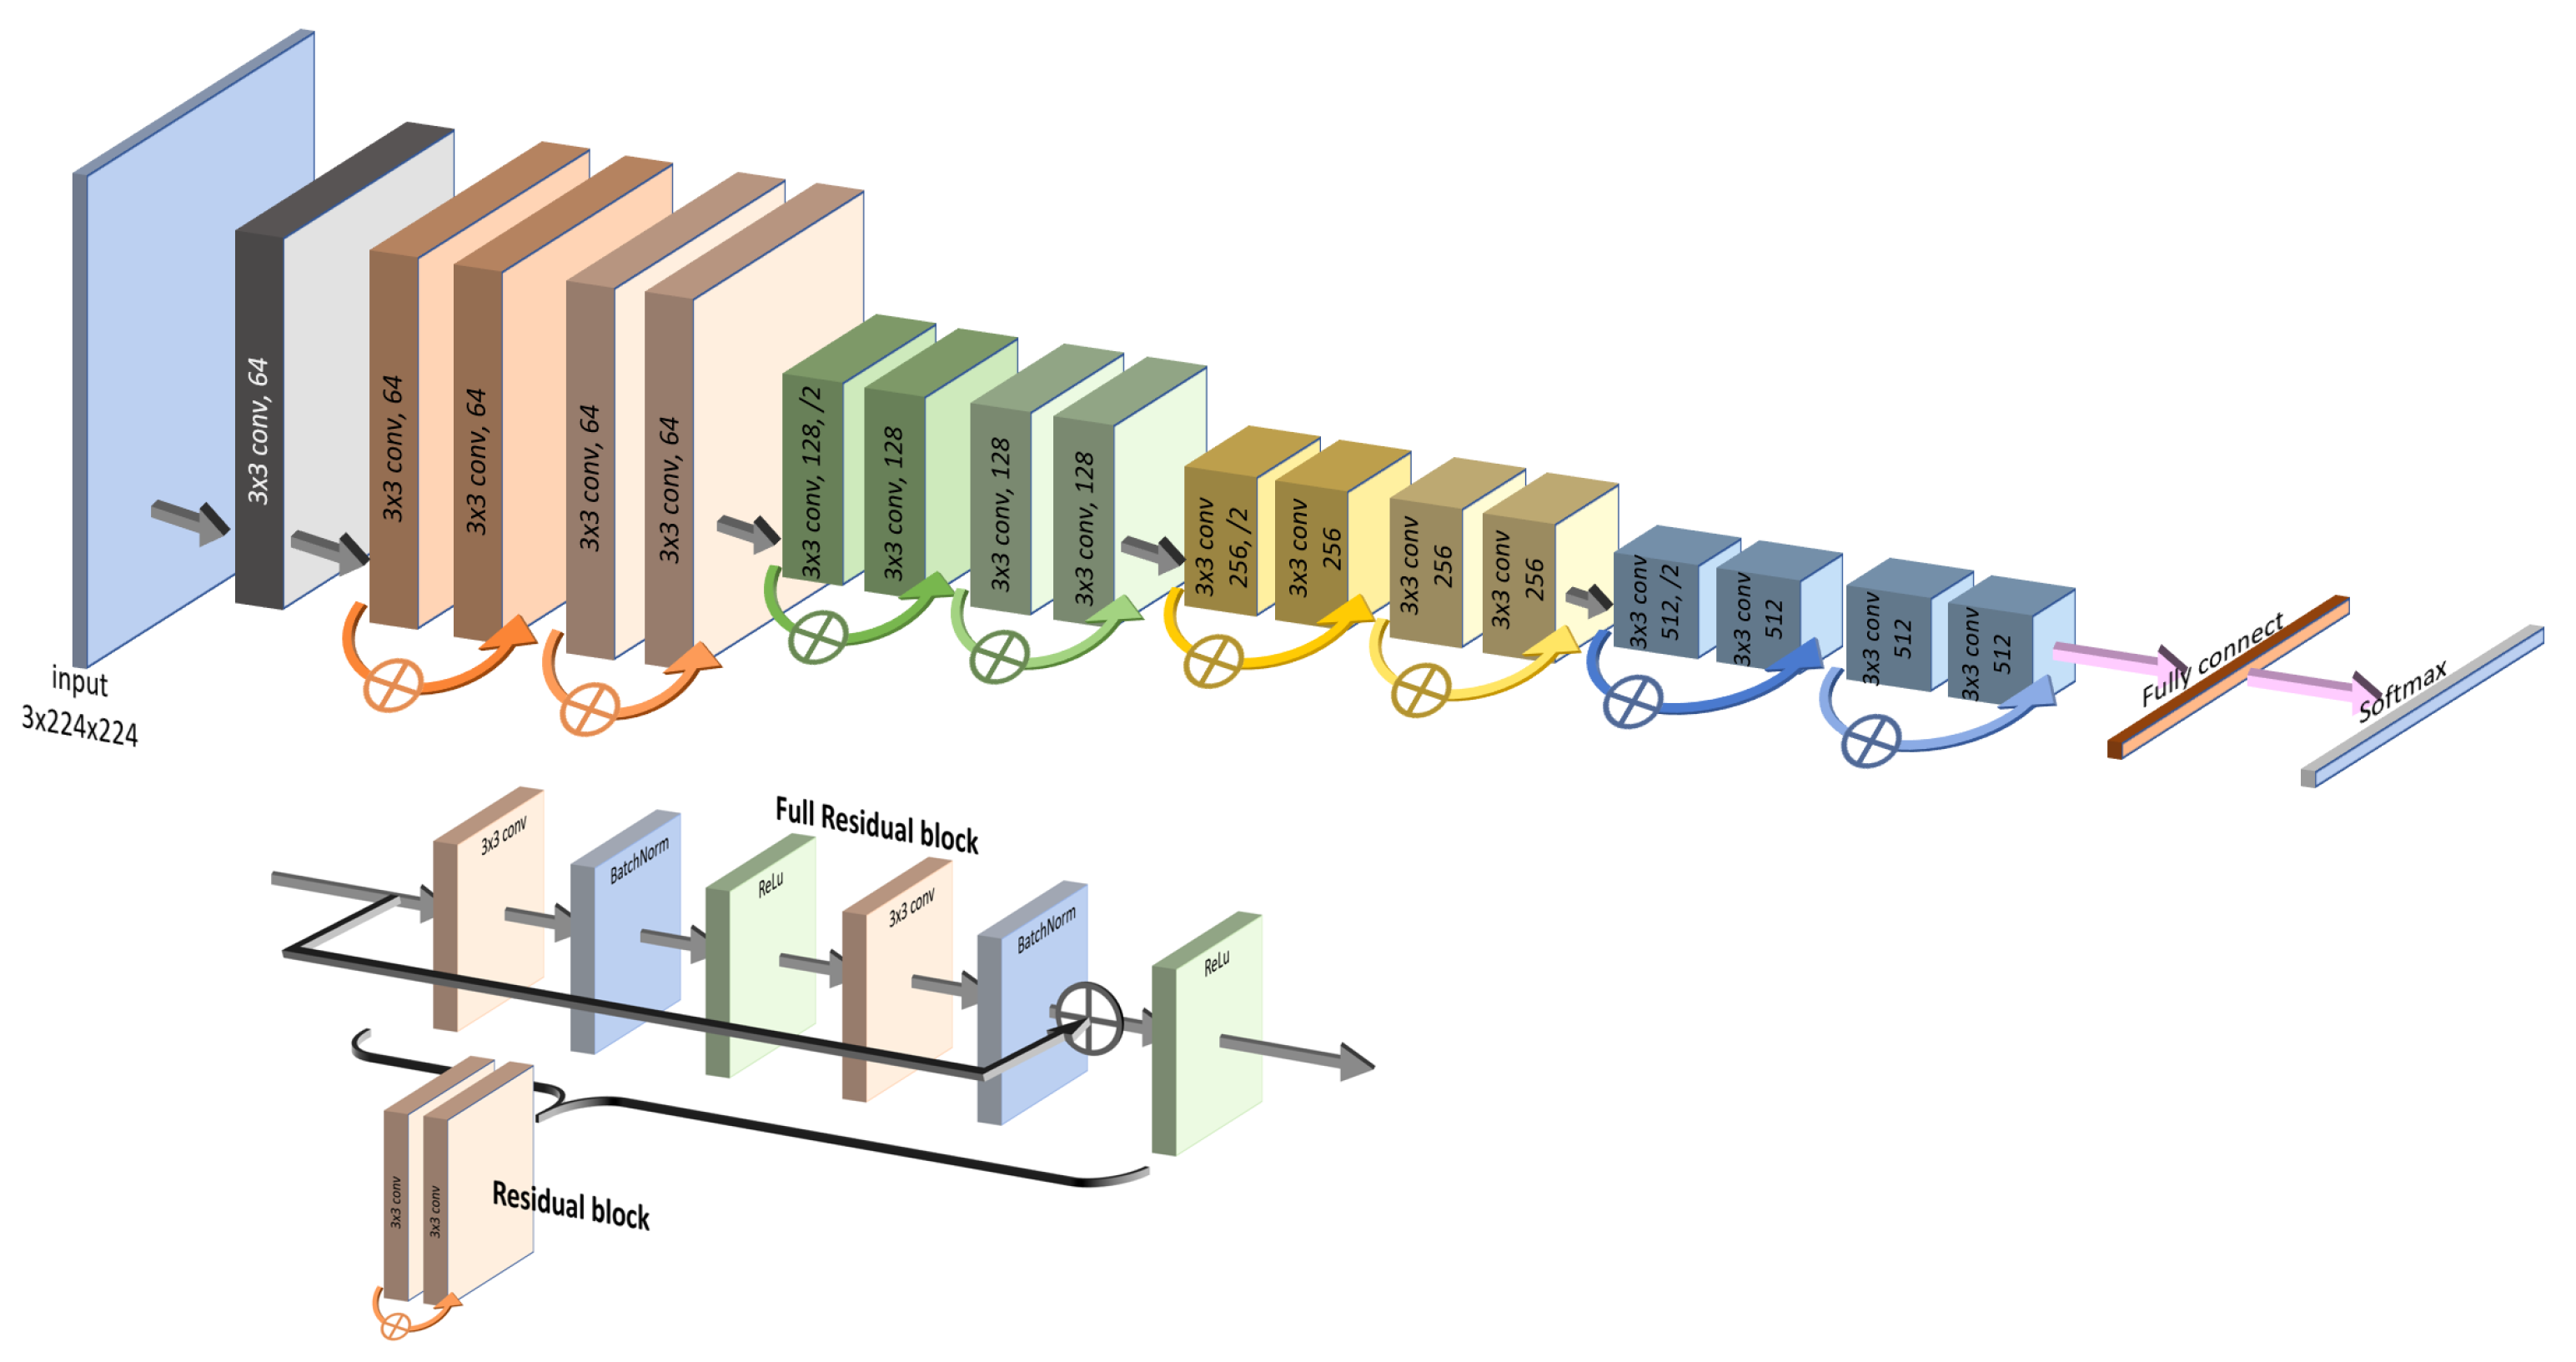

1. Pretrained Weights: Both ResNet50 and DenseNet201 come with weights learned through the large ImageNet dataset, allowing for increased model accuracy without requiring training from scratch;

2. Bypass Layers: The unique characteristics of both models lie in the specific structures of their “bypass” layers. ResNet50 utilizes skip connections that allow the input to jump over some layers, effectively shortening the path, as depicted in

Figure 3. This assists in capturing the latest layers’ features while mitigating the vanishing gradient problem.

3. Distinct Focus: We believe that the contrasting focus of ResNet50 and DenseNet201 can provide complementary insights. While DenseNet201 emphasizes the details from the start, ResNet50 is more attuned to the latest layers. These differences may lead to varied results, enriching our understanding of thyroid nodule classification. These well-known and effective models, along with their respective bypass strategies, offer promising capabilities for our specific task, justifying their selection for this study.

Figure 3.

ResNet structure (top image). The ResNet model contains multiple residual blocks (bottom image), each with skip connections that allow the input to bypass one or more layers, focusing on more recent features.

Figure 3.

ResNet structure (top image). The ResNet model contains multiple residual blocks (bottom image), each with skip connections that allow the input to bypass one or more layers, focusing on more recent features.